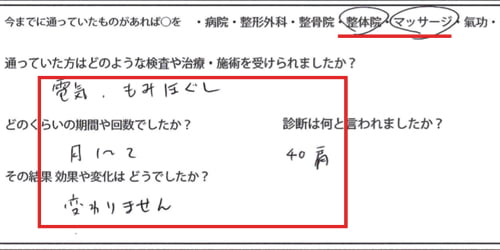

治療履歴・・・今までは電気治療やマッサージをして頂いていたようです。

筋肉に硬直やヨジレがある場合は電気治療や温熱、マッサージ、

リハビリなどで治ることは稀です。

実際にお身体の状態を診させて頂くとこんな感じでした。

Xは痛みの場所。赤い線は筋肉や腱の硬直やヨジレ。

顎下から鎖骨、そして肘に向かうラインに硬直やヨジレが集中しています。

そして首の後ろ側は脇の辺りまで硬直。